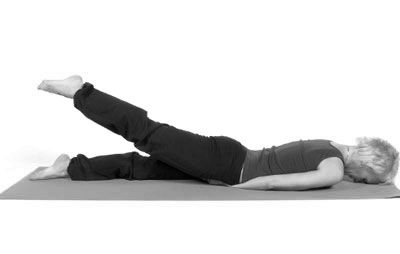

- З складених комплексів необхідно вибирати тільки ті вправи, які зміцнюють м'язово-зв'язковий апарат. Не примушуючи суглоби сильно рухатися, тобто на зміну звичним для більшості динамічних вправ приходять статичні.

- При недостатній фізичній підготовці пацієнта призначаються так звані щадні статичні вправи. Наприклад, якщо лежачи на спині підняти вгору ногу і тримати її на вазі хоча б 30 секунд, то м'язи неодмінно почнуть працювати, хоча суглоби рухалися мінімально.

- При артрозі важливо зміцнити м'язи, а не навантажити суглоб, тому виконуються переважно статичні вправи, коли положення фіксується протягом певного часу. Динамічні руху виконувати можна, але робляться вони плавно, без ривків.

- Ляжте на підлогу животом вниз. Ноги зведіть разом, руки витягніть уздовж тіла. Плавно підніміть ногу вгору, наскільки дозволяє вам стан організму. Зафіксуйте положення на 5-7 секунд. Плавно опустіть ногу на підлогу. Повторіть з іншою ногою. Зробіть по 5 разів кожною ногою, піднімаючи кінцівки виключно за допомогою кульшових суглобів і повністю розслабляючи ноги в момент їх знаходження на підлозі.

- Ляжте на лівий бік. Зігніть праву ногу в коліні. Витягнуту праву ногу підніміть і потримайте до 30 секунд. Потім опустіть ногу і розслабтеся. Повторіть по 5 разів з кожною ногою.